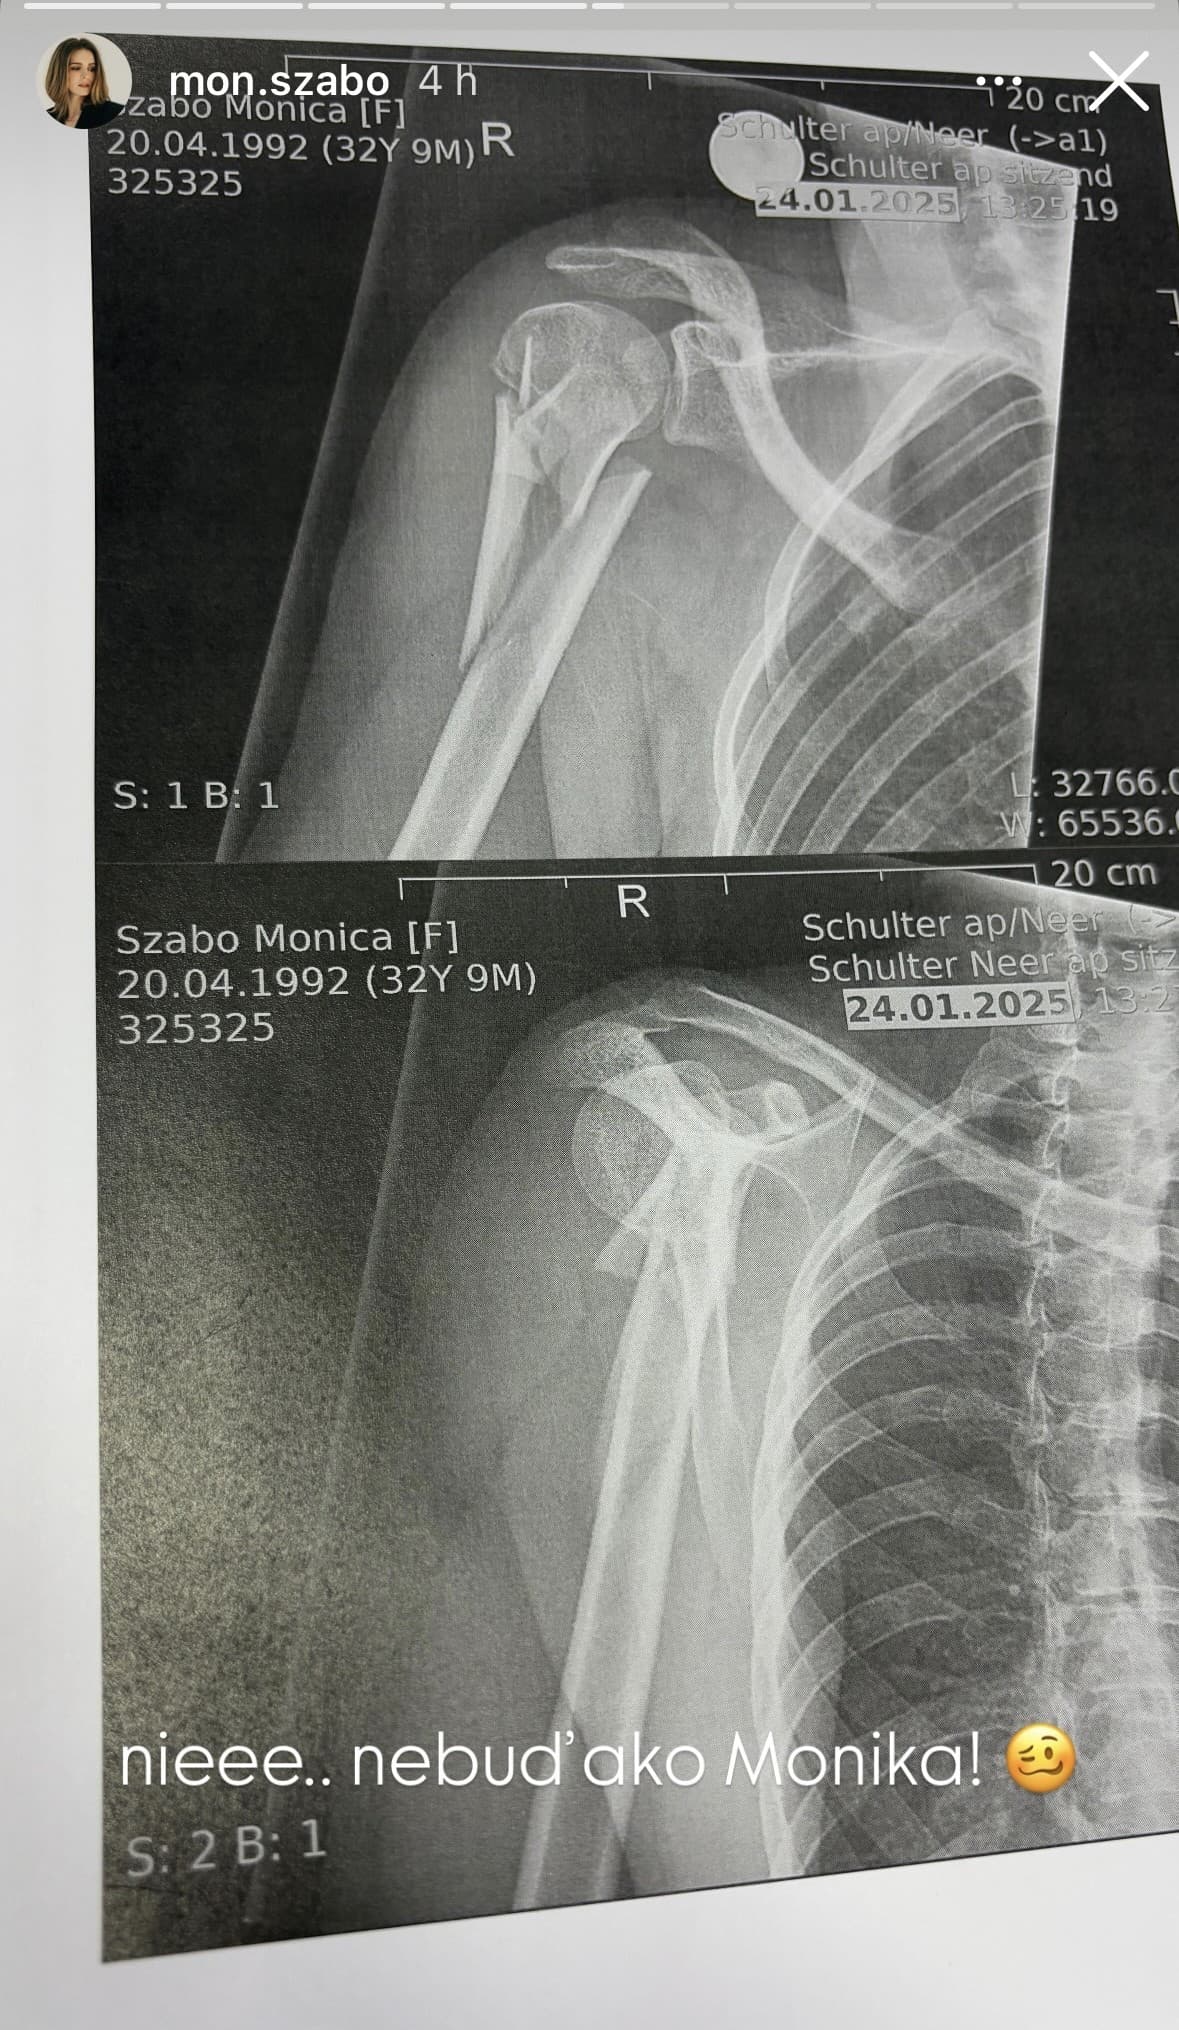

Pre web markiza.sk opísala, čo sa stalo. „Momentálne som v starostlivosti špičkových švajčiarskych lekárov a starajú sa o mňa úžasne. Operácia pomerne komplikovanej zlomeniny dopadla dobre a cítim sa podľa možností fajn," povedala. Na Instagram pridala tiež snímku z röntgenu. „Nieee, nebuď ako Monika," znel popis. Herečku teraz čaká rekonvalescencia. Prajeme skoré zotavenie!